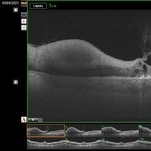

Swept source OCT angiography of a 58-year-old man with hemorrhage in his left eye.

Photographer: Nanda Lessi Hafni Eka Putri, MD (Ophthalmologist) & Ryan Mishbahuddin (Nurse), Ciawi General Hospital (Rumah Sakit Umum Daerah Ciawi)

Imaging device: DRI OCT Triton Plus (Topcon)

Condition/keywords: fundus photograph, optical coherence tomography (OCT)